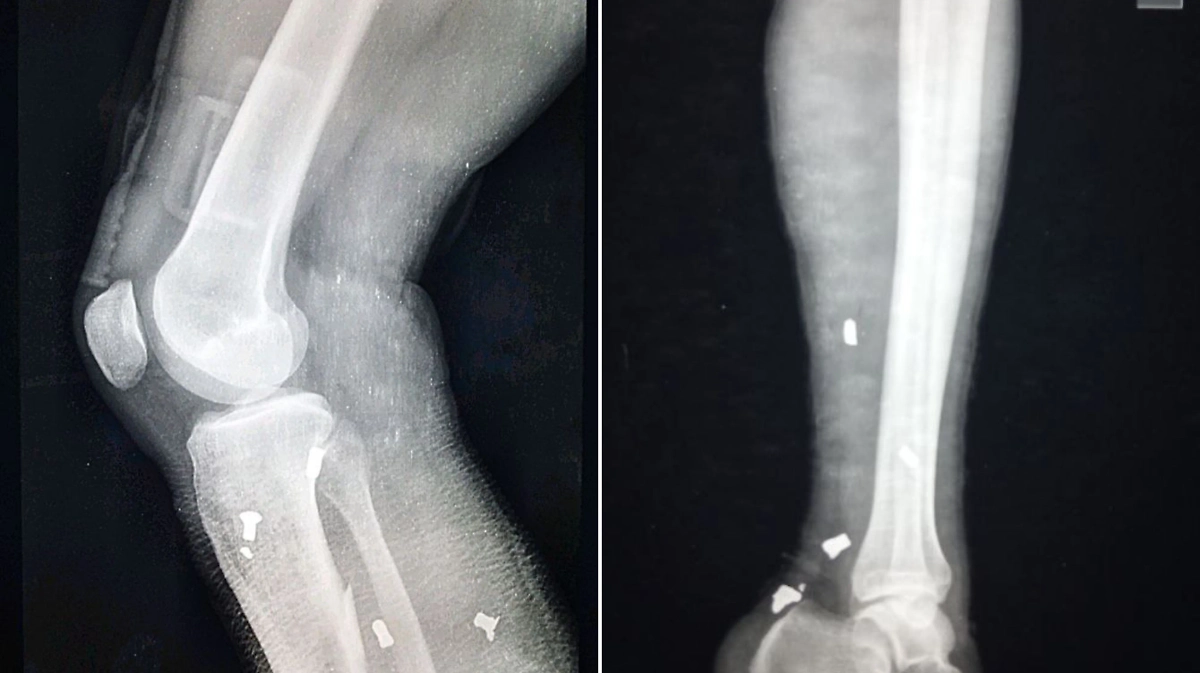

"Противник начал чаще применять самодельные взрывные устройства, где в качестве поражающих элементов использует винтики и болтики! Переход от националистической идеологии к методам и оружию террористов проходит весьма наглядно", — написал врач и приложил рентгеновские снимки российских военных, на которых видны поражающие элементы.

ВСУ стали использовать болты в качестве поражающих элементов. Фото © Telegram /КУЧИЦ Мед . KUCHITS MED